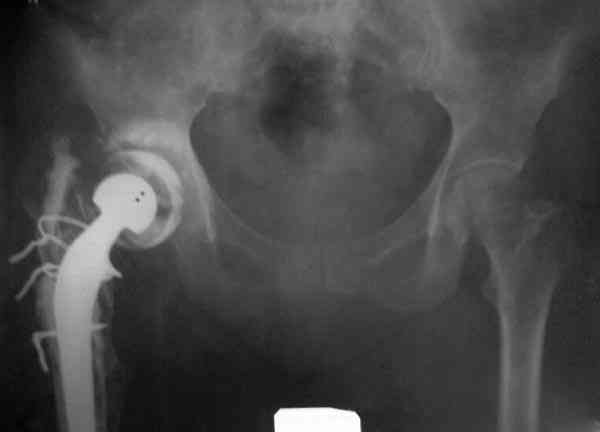

Наглухо ушитая рана с дренажом зажила первично, после чего с больной потерял контакт, и только недавно, через 8 лет я осмотрел её. Она без проблем нагружает на конечность и передвигается с помощью трости. От окончательной операции по реконструкции отказывается, довольная результатом.

Имеются литературные данные, когда спейсер держали не более 6 месяцев, но этот случай бьет все рекорды, может быть для наших людей, обременных финансовыми трудностями, нужна другая шкала оценки сроков нахождения спейсеров.

№3-6 снимки с осложнением

и последние снимки.